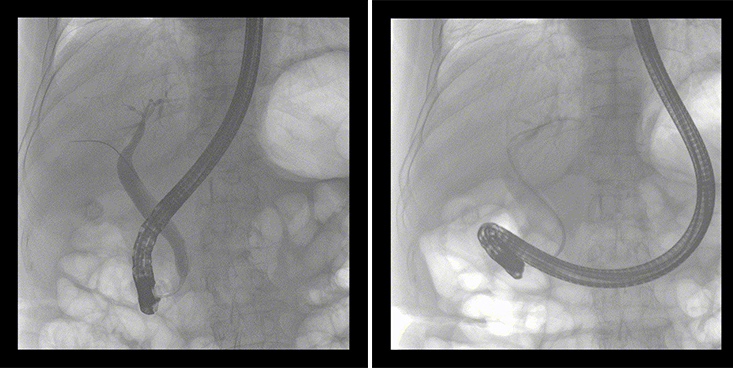

一位86歲的女性患者近來(lái)出現(xiàn)腹痛,入院后CT檢查并結(jié)合臨床表現(xiàn)被診斷為急性膽囊炎伴膽囊結(jié)石。經(jīng)專家團(tuán)隊(duì)協(xié)商并與患者家屬溝通,決定對(duì)患者實(shí)施經(jīng)內(nèi)窺鏡逆行胰膽管造影(ERCP)。

ERCP(經(jīng)十二指腸鏡下逆行胰膽管造影)現(xiàn)已成為比較成熟的微創(chuàng)介入技術(shù),被廣泛的應(yīng)用于臨床,ERCP也是消化內(nèi)鏡領(lǐng)域難度大、風(fēng)險(xiǎn)大、技術(shù)復(fù)雜的微創(chuàng)手術(shù),其并發(fā)癥多為致命性,ERCP手術(shù)對(duì)醫(yī)生的要求很高,因此,ERCP醫(yī)生又被稱為“刀尖上的舞者”。因?yàn)槭中g(shù)難度較大,過(guò)程復(fù)雜,需要C形臂精準(zhǔn)的配合,對(duì)影像清晰度的要求也非常高。

普愛(ài)醫(yī)療移動(dòng)式平板中C為本次ERCP手術(shù)提供實(shí)時(shí)無(wú)損高清影像,幫助醫(yī)生精準(zhǔn)定位?!俺上裥Ч浅0簦⊥耆惠攪?guó)際大牌的醫(yī)學(xué)影像設(shè)備……”鼓樓醫(yī)院江北國(guó)際醫(yī)院內(nèi)鏡中心手術(shù)團(tuán)隊(duì)對(duì)普愛(ài)醫(yī)療移動(dòng)式平板中C的成像效果給與了高度的評(píng)價(jià)。

在消化內(nèi)科主任的領(lǐng)導(dǎo)和多科室全力配合下,南京鼓樓醫(yī)院江北國(guó)際醫(yī)院成功完成了首例ERCP手術(shù)。